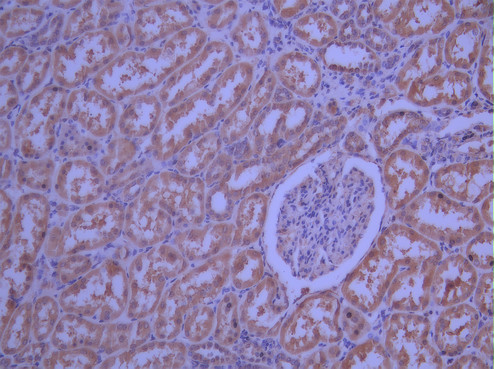

IHC image of CSB-RA272525A0HU diluted at 1:100 and staining in paraffin-embedded human kidney tissue performed on a Leica BondTM system. After dewaxing and hydration, antigen retrieval was mediated by high pressure in a citrate buffer (pH 6.0). Section was blocked with 10% normal goat serum 30min at RT. Then primary antibody (1% BSA) was incubated at 4°C overnight. The primary is detected by a Goat anti-rabbit polymer IgG labeled by HRP and visualized using 0.05% DAB.